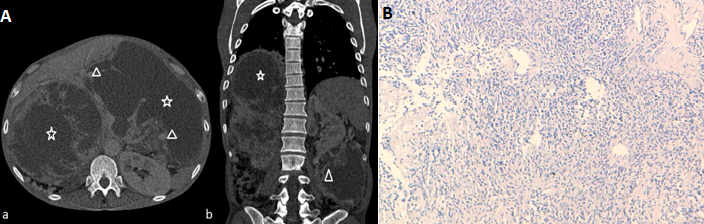

We describe a case of a 53 years old patient who underwent right nephrectomy for a renal tumor in 2005. The histological examination revealed an hemangiopericytoma with graveness signs. Ten years later, the patient developed a huge abdominal mass. CT scan showed a voluminous locally advanced tumor measuring 30*20 cm. The mass was multilobed and hypervascularized (A) Witch was compatible with a hemangiopericytoma. The biopsy confirmed the recurrence of the hemangiopericytoma (B). The patient received a palliative chemotherapy taking into consideration local and metastatic extension. Hemangiopericytoma is a rare vascular tumor that emerges from Zimmerman perocytes. Usually it’s a voluminous asymptomatic mass with variable malignancy potential, and no specified clinical or radiological aspects. The standard of care is surgery and it should be suggested even for recurrences, the management of locally advanced and metastatic disease consists on palliative chemotherapy for sarcoma and should be discussed in a pluridisciplinary reunion.